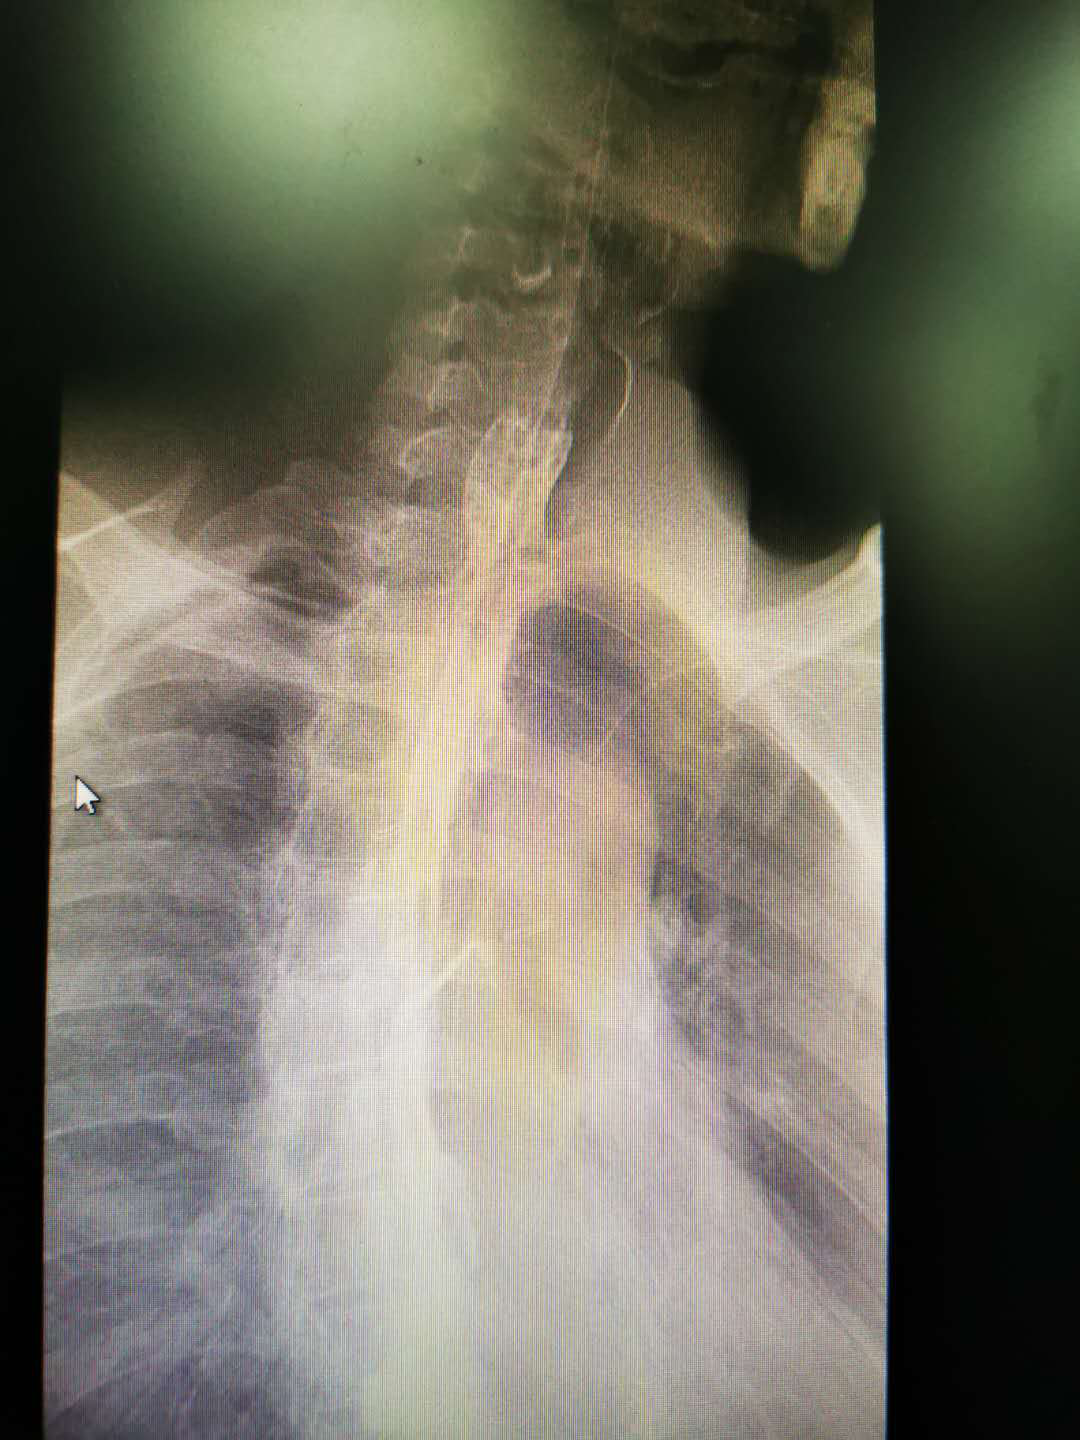

术后食管造影: